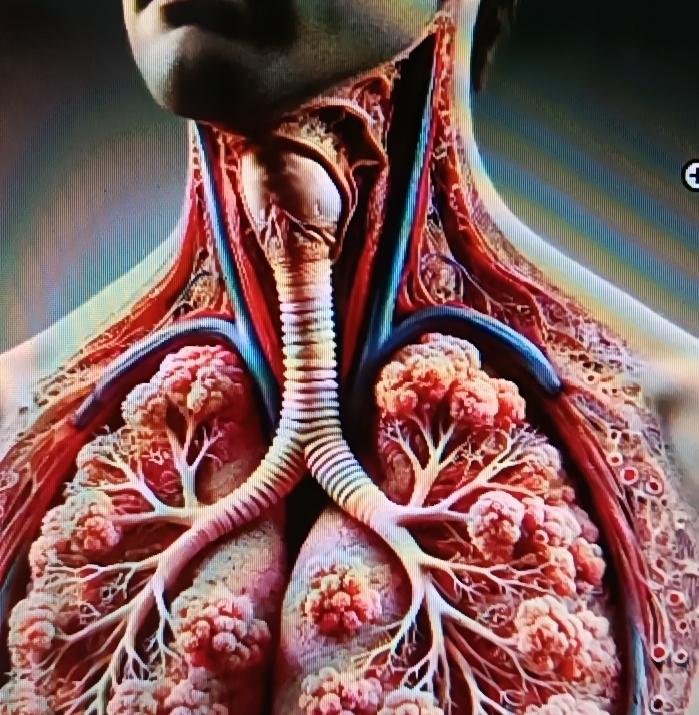

“意想不到有危险⚠️”湖北武汉,一名女子近两年来反复咳嗽、咳痰,不是感冒发烧,嗓子也不痛不痒。近日去医院做检查时发现右下肺支气管深处竟有2块小塑料片。正是这两块塑料片导致她两年反复咳嗽。 现在好多的食品都是即食零食,打开塑料外包装就可以品尝到美味了。打开方式各种各样,有手撕的,有用工具的,更有甚者用牙齿去咬。但方便的同时,也带来了意想不到的危险! 据媒体报道,湖北武汉的李女士从两年前就有点咳嗽,她也没放在心上,以为自己着凉了,引发了炎症,到药店买了点消炎药来吃,吃了几天也就好了。后来多次出现这种情况,李女士便习以为常。 今年冬天,李女士的咳嗽加重了,但除了咳嗽还是没有别的。李女士还是认为自己体寒造成的,便去看了中医,开些中药来调理。 刚开始喝中药时确实有效果,但疗程一结束便复发。 近日,她的咳嗽越来越重,咳出的痰里偶尔还带些血丝。家人劝她赶紧去大医院做检查,劝她有病不能拖,趁着治疗。 李女士到医院一检查,医生发现她右肺下支气管里竟然有两片异物,正是这异物卡在气管里导致她咳嗽。医生通过气管镜手术把异物取出来一看,原来是两块塑料片,塑料片在气管里已经被磨平了棱角! 原来李女士平常在家喜欢吃些袋装的零食,撕不开袋子的时候就用牙齿去咬,有时候碎成小块的塑料袋就随着呼吸进到了气管里。经过治疗,李女士已经康复。 网友:我以前也经常这么干,撕不动就咬开,看了这个视频,以后再也不敢了。 取材网络,侵删